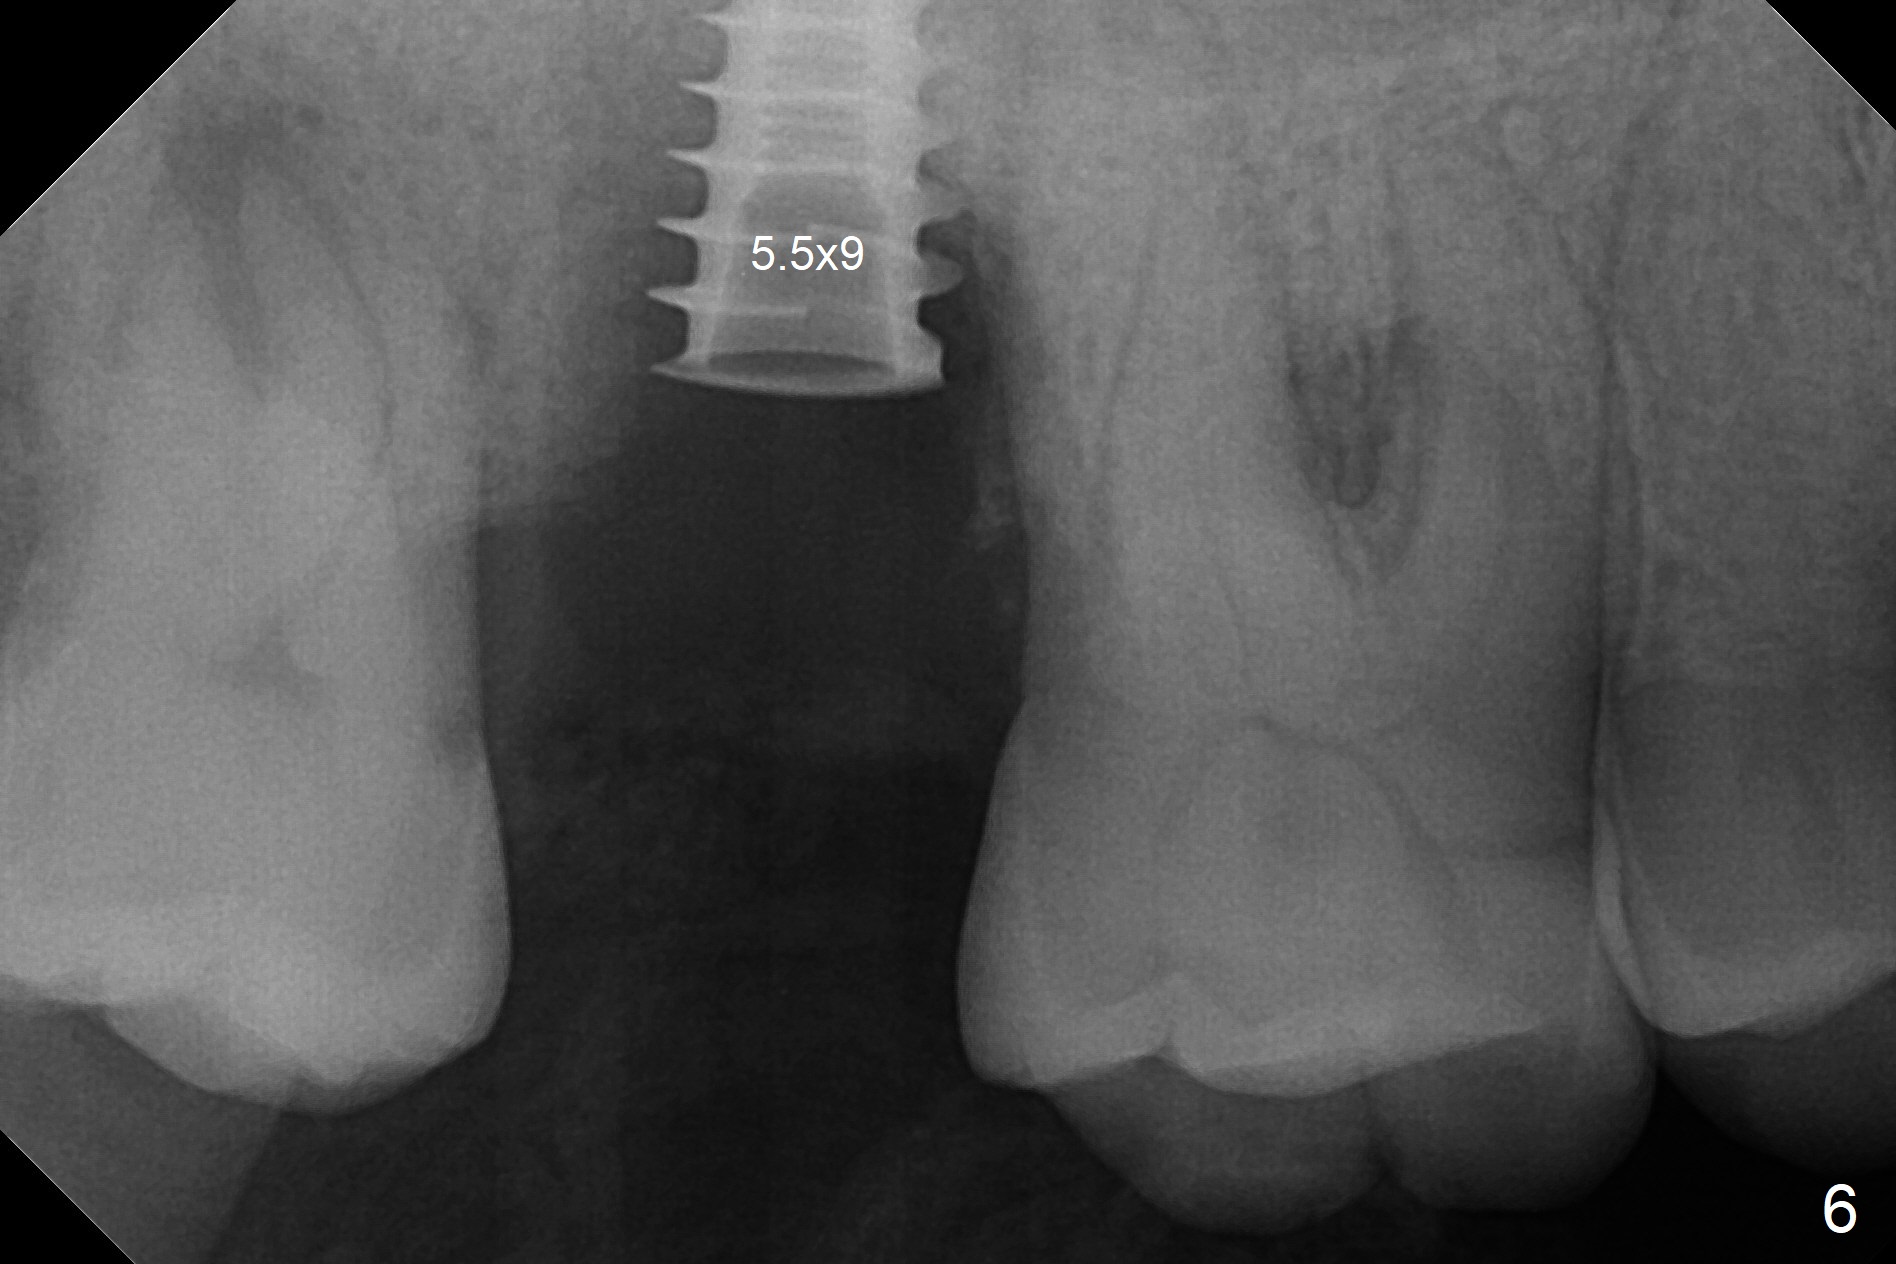

When the 59-year-old man returns for #24 implant placement, the tooth #2 is found to have crack (Fig.1,2 arrowheads), associated with buccal and palatal fistulae (*) and loss of amalgam (Fig.4 *). Abundant granulation tissue is attached to the roots of the affected tooth (Fig.3), indicating severe bone loss. There is a plateau associated with the septum and buccal sockets, which is the site of osteotomy. Magic split and 3 and 3.8 mm Magic Expanders are used to initiate osteotomy. After use of 4.3 mm Magic Drill for about 3 mm, Osteogen plug and allograft are used for sinus lift, followed by insertion of a 4.5x11 mm dummy implant (Fig.5). When a 5.5x9 mm dummy implant is placed with stability, it appears to be seated cervical (Fig.6,7). When a 6x9 mm IBS implant (definitive) is placed with a 6.5x5.5(4) mm abutment, they are seated too deep for provisional (Fig.8). The implant/abutment are removed and replaced by a 6.5x11 mm one in a shallower position; after trimming the same abutment as mentioned above (Fig.9), an immediate provisional is fabricated to keep bone graft in place. Fabrication of Tap with soft tissue markers will reduce the chance of miscalculation and waste of implants. The coronal threads of the implant are covered with bone 6 months postop (Fig.10). One month later when a permanent crown tries in, the implant is found to be loose and tender. A healing abutment is placed. Six months later, the patient returns for crown retry-in. The tooth #1 seems to have shifted mesially (Fig.11 arrow). When the abutment is placed, the implant remains tender and loose. After implant removal with a wrench, there is no granulation tissue or bony defect, including the intact sinus floor (Fig.12 <). Since the tooth #1 has deep periodontal pockets and mobility, the tooth is extracted with abundant granulation tissue. After debridement, Osteogen plug is placed in the socket of #1, while Vanilla graft is placed at the site of #2 (Fig.13 *). Three weeks later, the socket of #2 heals with exposure of Osteogen plug (Fig.14 (B: buccal)).